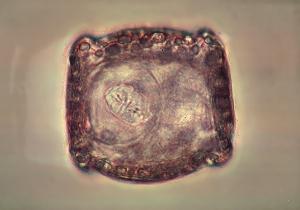

5- Ténias : Anoplocephala perfoliata (+ Anoplocephala magna et Paranoplocephala mamillana)

Photo Laboratoire Mérial

Morphologie : Vers plats, blancs, aux segments larges et mais très courts (aspect très plissé) (10-20 mm de large pour 1-2 de haut). De 4 à 8 cm de long pour A.perfoliata, 20-80 cm pour A.magna, et 1-5 cm pour P.mamillana.

Segments fragiles, libérant des œufs : 50-80 µm de diamètre, quadrangulaires à semicirculaires, à paroi épaisse à stries et renfermant un embryon hexacanthe (6 crochets) au sein d'un appareil piriforme.

Localisation : Iléon, valvule iléocaecale pour A.perfoliata, fixation par le scolex pourvu de 4 fortes ventouses.

Epidémiologie : Cycle passant par un acarien Oribatidae hôte intermédiaire hébergeant une larve cyticercoïde infestante pour les Equidés. Développement du strobile en 4 à 6 semaines chez le cheval, longévité de 4 à 6 mois. Passage de l'hiver sous forme larvaire chez les oribates. Infestations du printemps à l'automne.

Etude clinique : Coliques d'intensité variable, dysfonctionnement de la valule iléocaecale avec rétention alimentaire dans l'intestin grêle, possibilité de développement d'un fibroleiomyome de cette valvule.